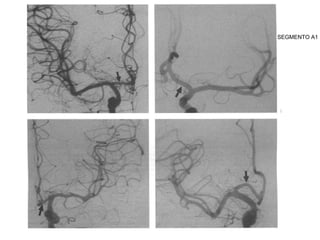

SEGMENTO A1

• A1 (pré-comunicante): . acima do quiasma óptico até unir-se

a AComA. A hipoplasia desse segmento correlacionasse

com a formação de aneurismas.